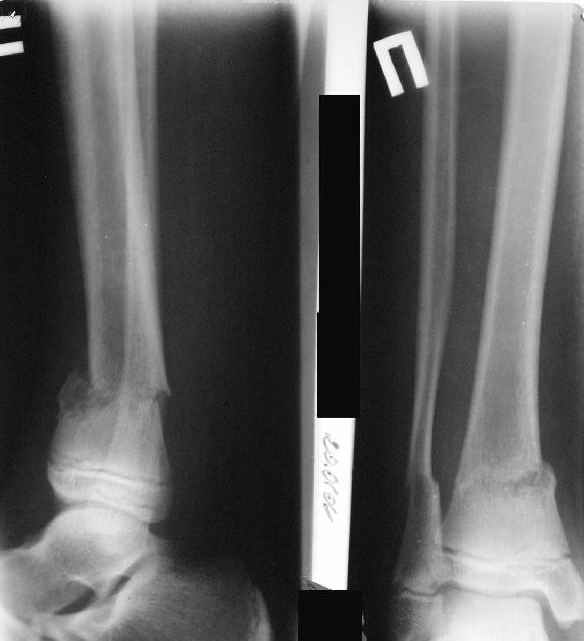

A>> Перелом костей н\3 правой голени со смещением.

AVM> Это от 13.10.04? А это близкие к первичным снимки?

Есть даже тень периостальной костной мозоли и сросшийся перелом

малоберцовой кости.

Деформация появилась и наростала во времени при фиксации в гипсовых повязках.

Это сросшийся перелом малоберцовой кости. И ложный сустав

н\3 б\берцовой кости.

Так как речь зашла непосредственно о травме, см этапные

снимки. Как все было

Первичные

|